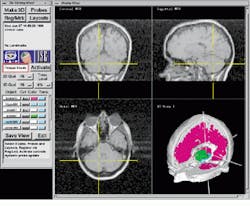

In the Viewing Wand system, a hand-held probe from Faro (Lake Mary, FL) is attached to the operating table via a mechanically linked arm (see Fig. 1). Transducers located in each of the arm`s six joints collect and send positional and directional vector information to an IBM 386 PC. There, rotational and translational data of the probe are calculated using a DSP-based add-in board. Positional information is then sent over an RS-232 serial link to a 715/100 Hewlett-Packard (Palo Alto, CA) graphics workstation, where axial, coronal, sagittal 2-D, and reconstructed 3-D images are displayed simultaneously (see Fig. 2). Running under UNIX OS, the workstation is configured with a 96-Mbyte RAM and a 2-Gbyte disk for image storage.

FIGURE 1. By placing a hand-held probe inside a patient`s brain during surgery, the physician can automatically retrieve cross sections and a three-dimensional reconstruction of the patient`s brain.

FIGURE 2. Using the ISG Viewing Wand system during surgical procedures, physicians can examine coronal (top left), sagittal (top right), and axial (bottom left) MRIs of the patient`s brain. Reformatted 2-D MRI slice data are displayed as a 3-D object in the lower right quadrant.